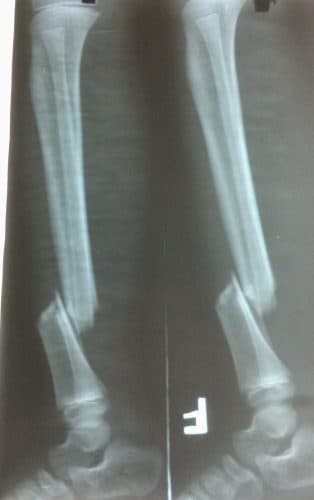

- Triệu chứng trên X-quang: Cần chụp X – quang hai tư thế thẳng và nghiêng, chụp toàn bộ cẳng chân lấy cả khớp gối và khớp cổ chân. Hình ảnh trên X-quang cho thấy rõ vị trí của xương chầy và xương mác, hình thái đường gãy và mức độ di lệch.

Hình ảnh trên X-quang cho thấy rõ vị trí của xương chầy và xương mác, hình thái đường gãy và mức độ di lệch.